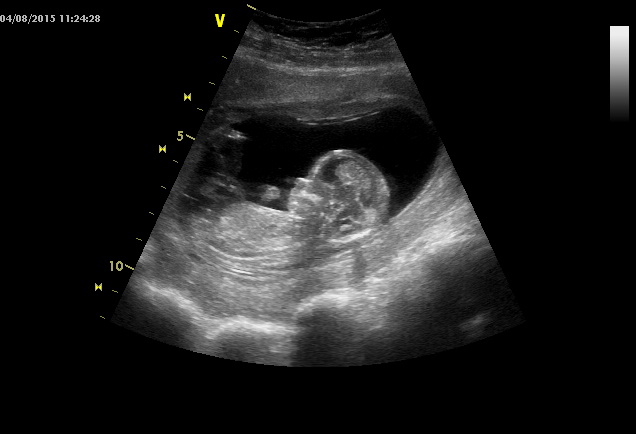

Dnes na kontrole vše v pořádku, opět mi udělala doktrorka rychlý UZ, malej snad poprvé spinkal, ruce před obličejem. Řekla mi, ať už zas beru jen jedno magnézko denně, pokud je to klidné, abych prý neměla průjem. To mi teda asi nehrozí

. Malému naměřila asi 914 g, takže o dost míň než včera doktor (990). Aspoň vidíte, že je to jen orientační měření, plus mínus autobus

A tady jsou některé fotky ze screeningů